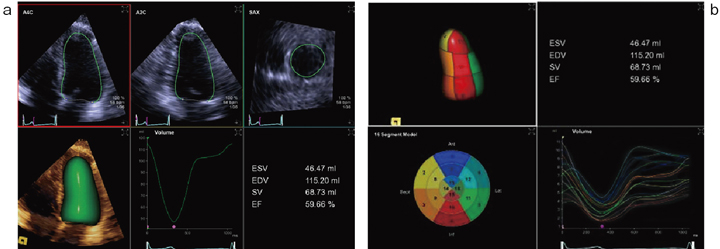

eSie LVAを起動させれば,左室全体の1心周期にわたるトレースが,わずか20秒程度で完了し,時間容量変化曲線と,拡張・収縮末期容積,駆出率などが表示される(図3)。輝度情報だけでなく,データベースを組み合わせ,自動化することで計測結果の施行者依存性を低減させ,再現性・精度を向上させている。

図3 eSie LVAの解析結果の1例

わずか20秒程度で再現性・精度の高い左室容量の計測が可能である(a)。

左室16分画表示にも対応している(b)。